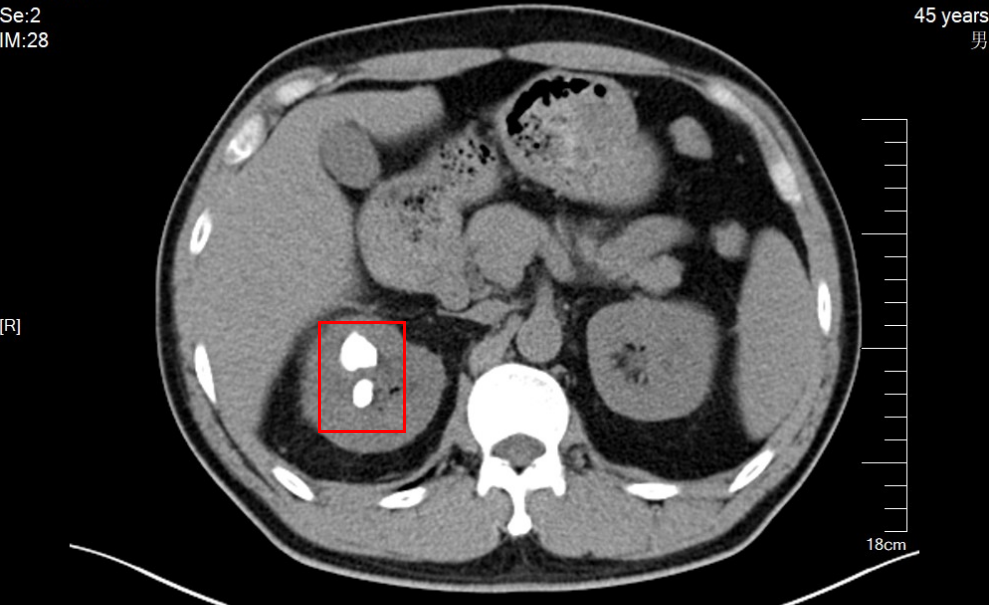

随后,科室内开展了深入的病例讨论。在李虎主任及黄志强副主任医师的带领下,团队仔细研判赵先生的影像资料,发现其肾脏结石分布广泛,且部分位置隐蔽,加上既往手术史,情况较为复杂。

经过严谨评估,泌尿外科专家团队最终为赵先生制定了个体化手术方案:实施“右侧经皮肾镜碎石取石术+智能控压联合可弯曲鞘输尿管软镜碎石清石术”,通过多镜联合的方式,力争一次手术清除所有结石。

手术当日,在麻醉医生与手术室护理团队的密切配合下,由黄志强副主任医师、申杨超主治医师、王宁宁主治医师共同操作,利用经皮肾镜处理主体结石,再联合可弯曲输尿管软镜精准追击藏于肾盏深处的小结石。智能控压系统实时监测并调节肾内压力,在高效碎石的同时最大限度保护肾脏功能,降低感染风险。整台手术过程顺利,结石被彻底清除。